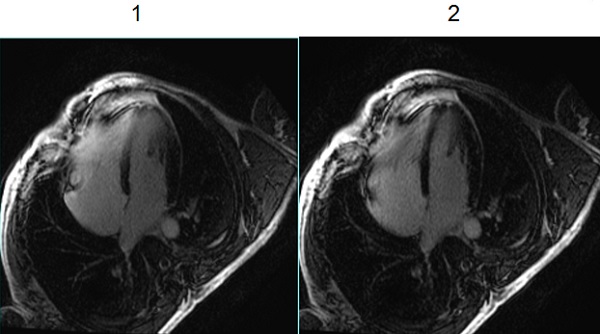

Use IR prep pulse type set to Enhanced with Myocardial Delayed Enhancement (MDE), Cine IR, Phase Sensitive MDE, and Single Shot MDE acquisitions. The User CV improves the robustness of the inversion in the presence of B1 and B0 homogeneity variations that can affect the IR pulse performance.

| 1 | Image with IR Prep Pulse type set to 0 (legacy). |

| 2 | Image with IR Prep Pulse type set to 1 (Enhanced), which demonstrates improved myocardial suppression. |